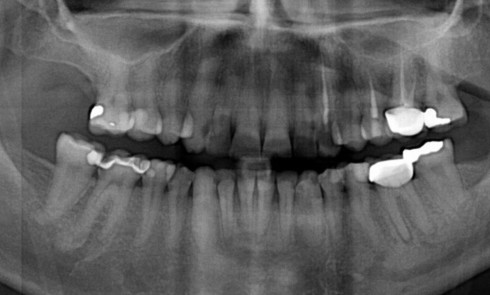

Article réservé à nos abonnés Traitement parodontal et restaurateur chez les personnes présentant un trouble des conduites alimentaires

Les troubles des conduites alimentaires (TCA) dont l’anorexie mentale et la boulimie sont des troubles graves, évoluant sur une longue...